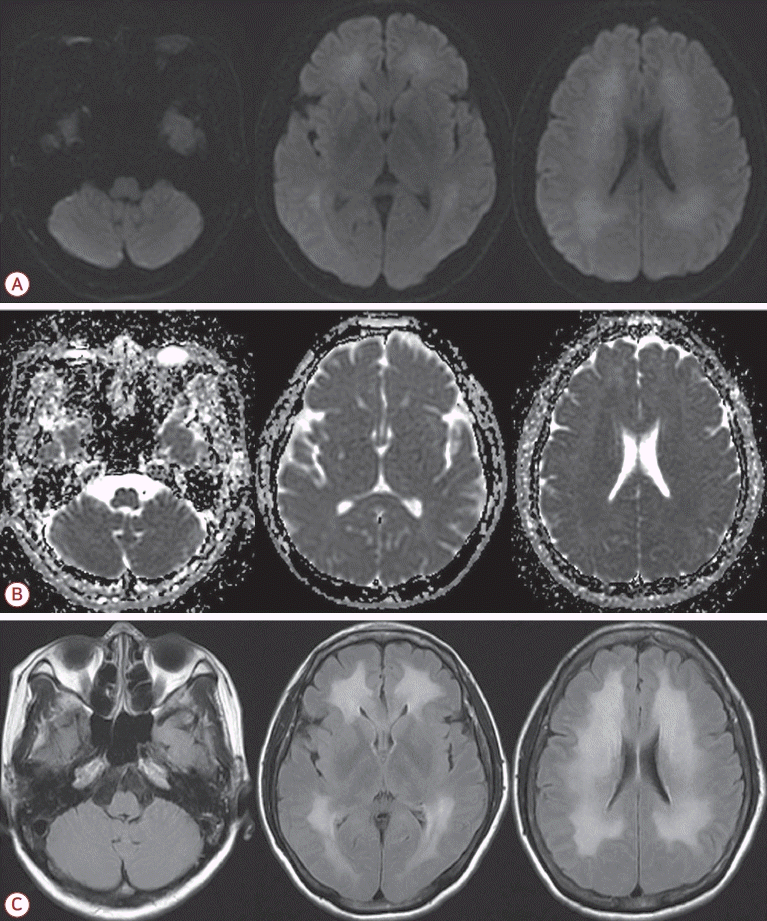

내원 당일 시행한 확산강조영상에서 양측 소뇌의 수평틈새 인근의 소뇌이랑에 대칭적인 고신호강도의 병변이 관찰되었다(Fig. 1-A). 이 병변은 겉보기확산계수지도영상에서는 저신호강도를 보였고(Fig. 1-B) 액체감쇠역전회복영상에서는 고신호강도를 보였다(Fig. 1-C). 그 외 다른 뇌 부위에서의 병변은 관찰되지 않았다(Fig. 1).

Brain magnetic resonance imaging of a patient with carbon monoxide poisoning. Diffusion-weighted imaging shows hyperintense lesions in the bilateral cerebellum along the horizontal fissure (A), corresponding to hypointensity on the apparent diffusion coefficient map (B), and hyperintensity on the fluid attenuated inversion recovery imaging (C). No abnormal signal changes are observed in other brain regions.

그러나 환자는 퇴원 2주 후부터 말수가 줄어들고 보행이 느려지며 종종걸음을 걷게 되었다. 또한 식사를 잘 하지 않으며 멍하게 있는 모습이 자주 관찰되었다. 이후로도 점차 악화되어 퇴원 3주째에는 자발적 행동이 거의 없어지고 누워 있으려고만 해서 다시 입원하였다. 신경계 진찰상 의식은 각성 상태였지만 말을 하지 않았고 질문에 대답하지 않았으며 명령 수행도 하지 않았다. 간이정신상태 검사(mini-mental state examination)도 시행하였으나 전혀 협조가 되지 않았고 대답도 하지 않아서 평가가 불가능하였다. 근력은 사지 모두 grade 3 정도로 양쪽 팔을 위로 올리는 것과 부축해서 서는 것은 가능하였으나 걷지는 못하였다. 손가락코 검사, 발꿈치정강이 검사, 일자보행 검사 등의 소뇌기능 검사는 협조가 되지 않아서 평가할 수 없었다. 통증 자극에 대한 반응이 양측에서 감소되어 있었고 사지에서 경축(rigidity)이 관찰되었다. 건반사는 사지에서 정상적이었고 바뱅스키징후는 관찰되지 않았다. 자기공명영상에서는 이전의 소뇌의 병변은 사라졌지만 새롭게 양측 피질하백질에 광범위한 고신호강도가 확산강조영상과 액체감쇠역전회복영상에서 관찰되었다(Fig. 2). 자기공명혈관조영 검사에서 뇌혈관의 이상 소견은 없었다.

Follow-up magnetic resonance imaging (MRI) performed 1 month later in the patient who developed delayed encephalopathy. MRI reveals diffuse high signal intensities in the bilateral periventricular white matter on diffusion-weighted imaging (A), with corresponding mixed signal intensities on the apparent diffusion coefficient map (B), and high signal intensities on fluid attenuated inversion recovery imaging (C).